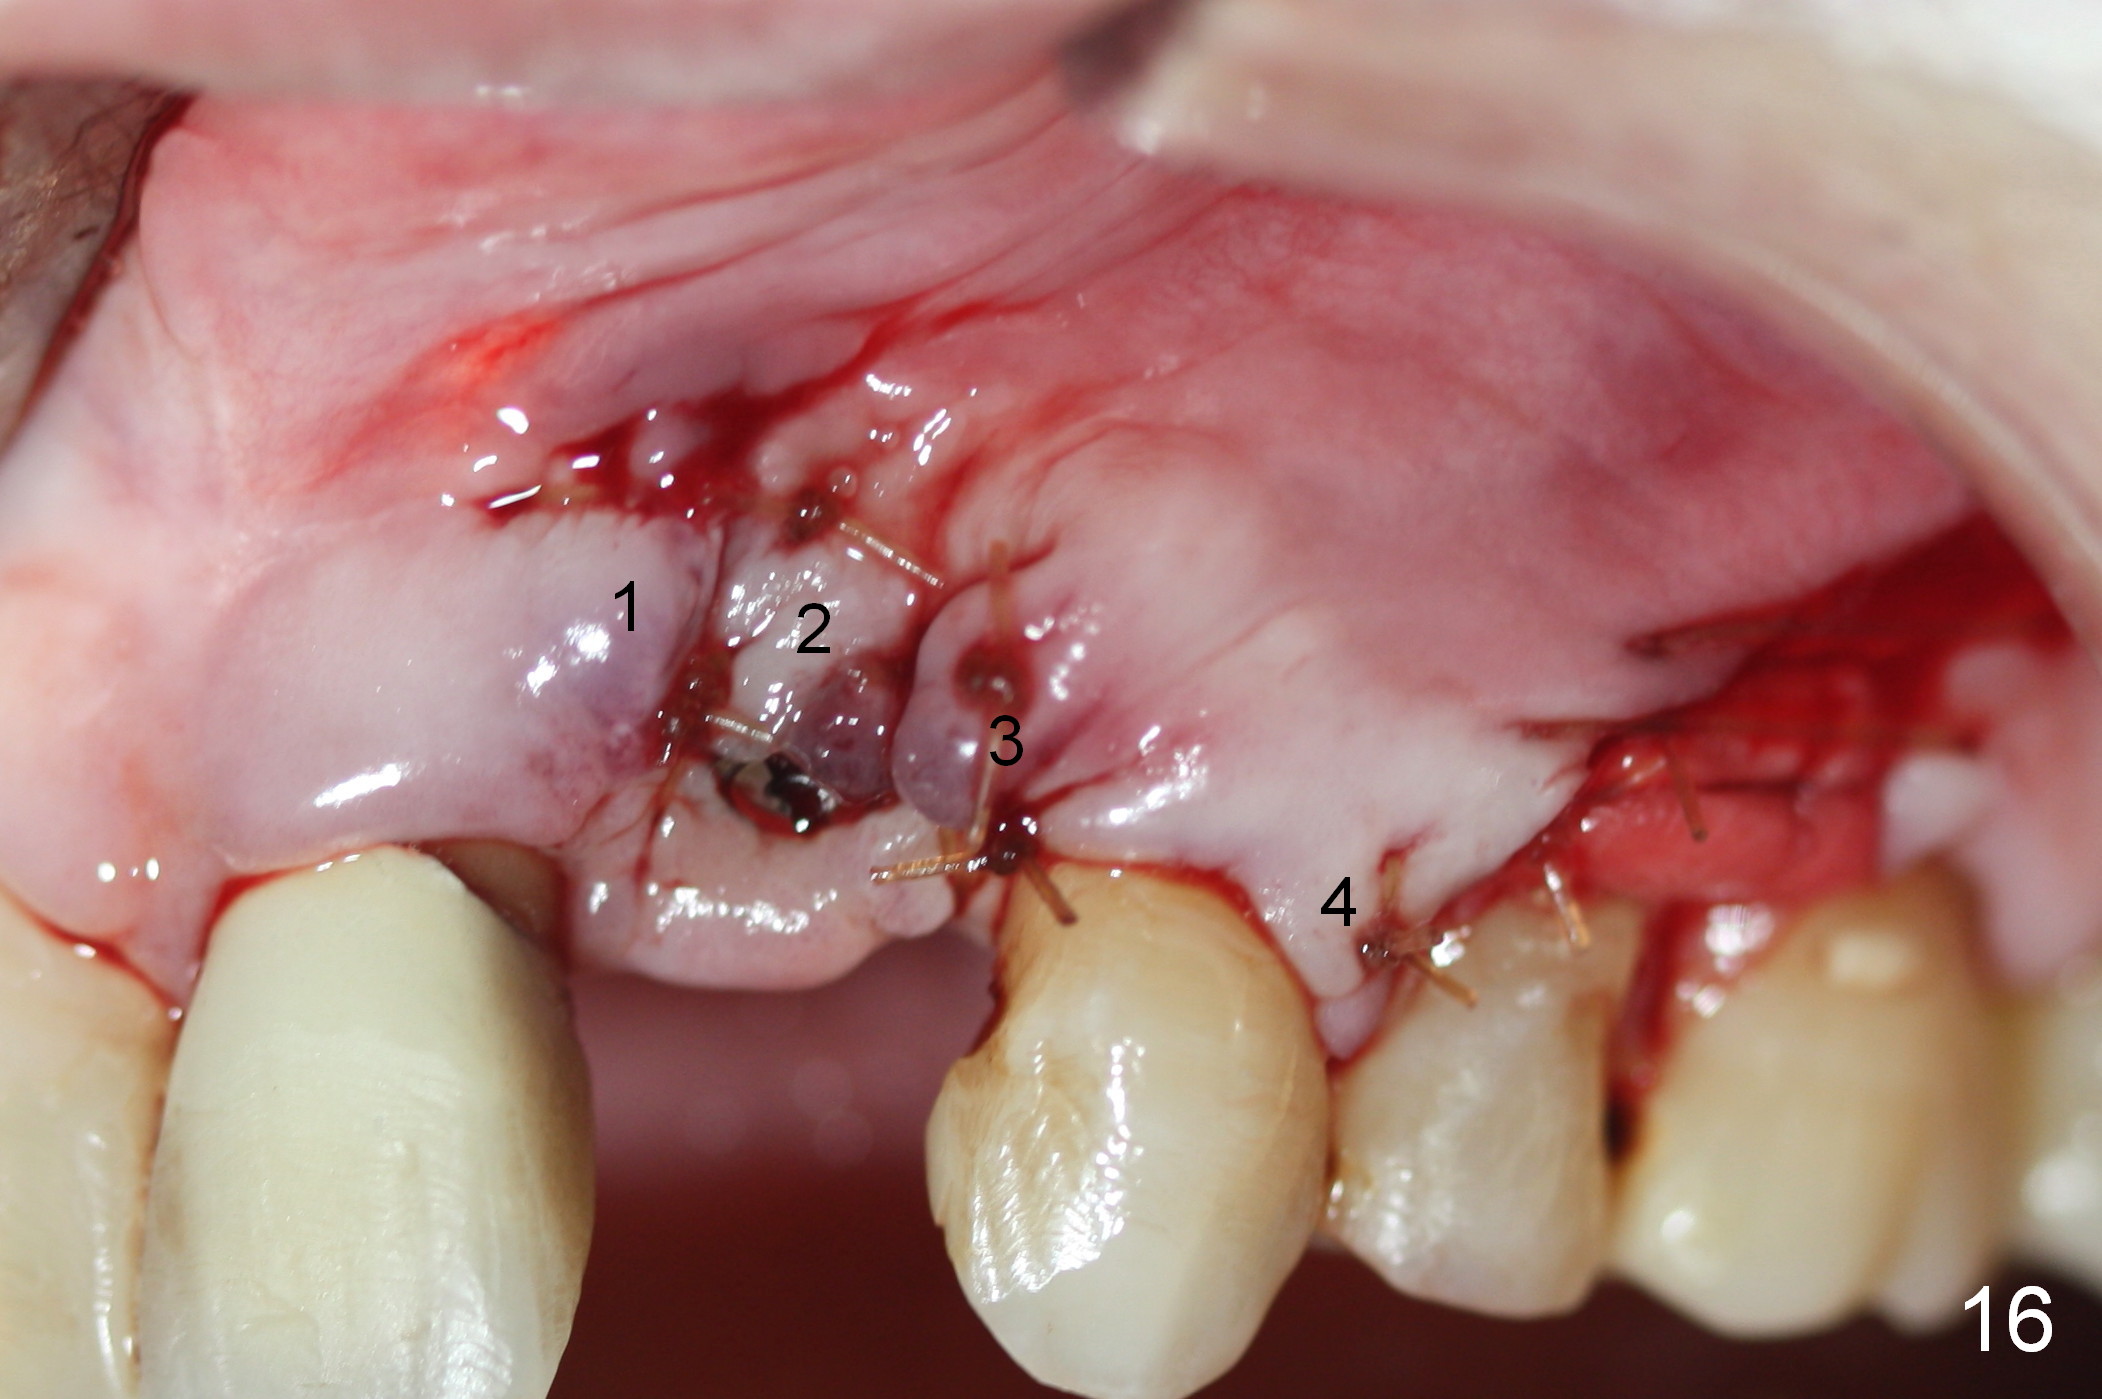

As expected, there is midbuccal tissue deficiency (Fig.9,10: 2 months postop). After discussion, a free gingival graft from the palate is placed (Fig.11,12 *). Two weeks later, the graft sloughs (Fig.13). A pedicled flap is designed (Fig.14) and transferred to repair the defect (Fig.15,16).